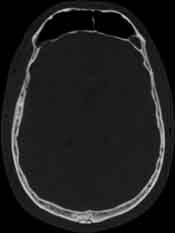

Visible Human male: Sectio transversalis 1080

CT